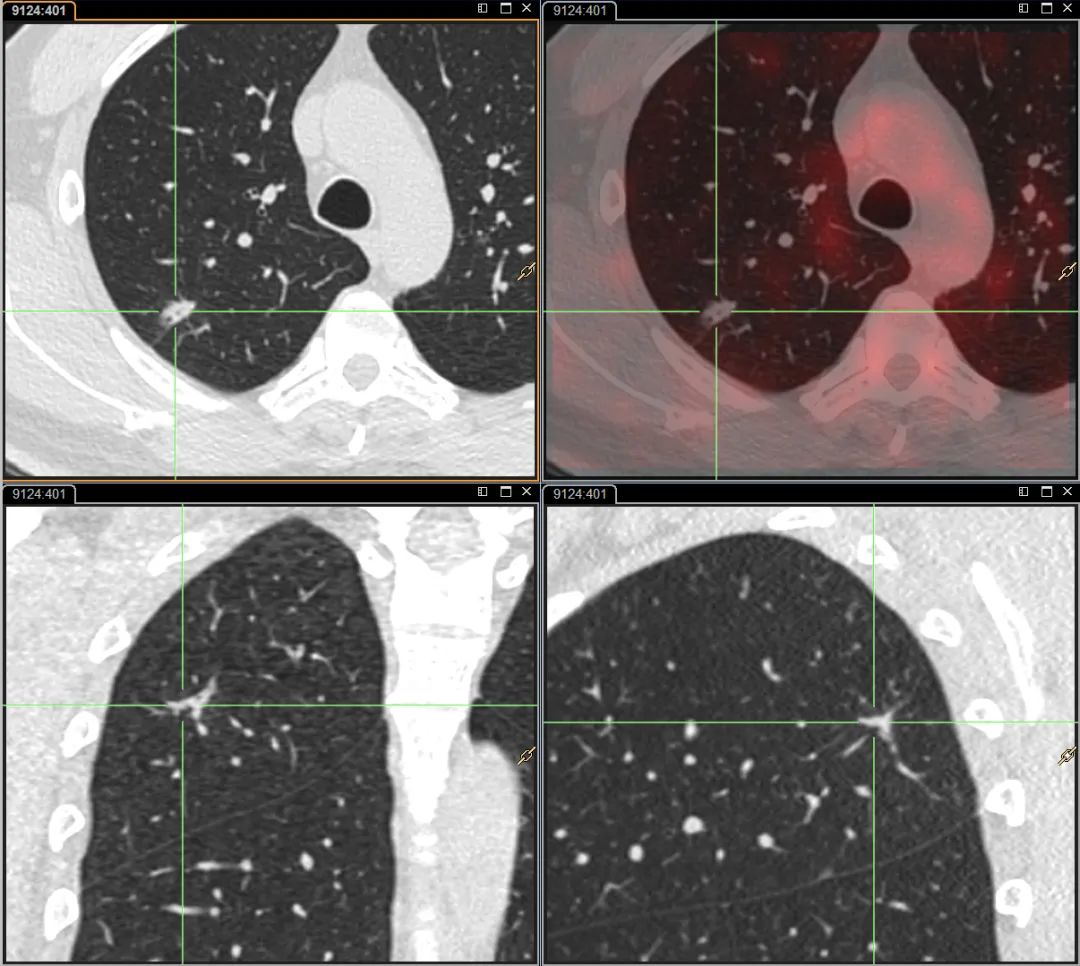

按临床医生要求,为了赶紧明确诊断,张先生到天津全景尽快进行PET/CT检查。

天津全景的影像医生仔细对比了本次CT影像与既往影像检查资料,发现病灶形态一年来没有明显变化,结合PET扫描SUV值较低且无明显代谢增高的情况,初步判断这是一个偏良性的病变。

按照天津全景“三级审核”制度,考虑临床意见全景又邀请天津三甲医院胸部影像权威的专家进行讨论会诊,结论得到了支持,考虑“良性瘤样增生”。